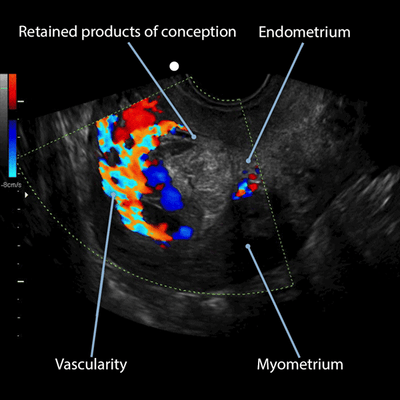

👩‍⚕️ Scanning & Imaging Tips: Using Color Doppler Imaging to Identify Retained Products of Conception

The diagnostic accuracy of ultrasound for detecting retained products of conception is substantially increased when color Doppler is used to assess for increased vascularity. 1, 2 Increased vascularity is related to persistent vascular connectivity between the uterine vasculature and retained placental tissue in retained products of conception. Increased vascular flow is typically demonstrated within the surrounding myometrium and into the endometrium. The accompanying transvaginal ultrasound images, taken in a midsagittal view of the uterus, are from two different patients and show retained products of conception with type 3 vascularity. Note that the increased vascularity arises from the myometrium and extends into the endometrium, distinguishing it from an arteriovenous malformation.